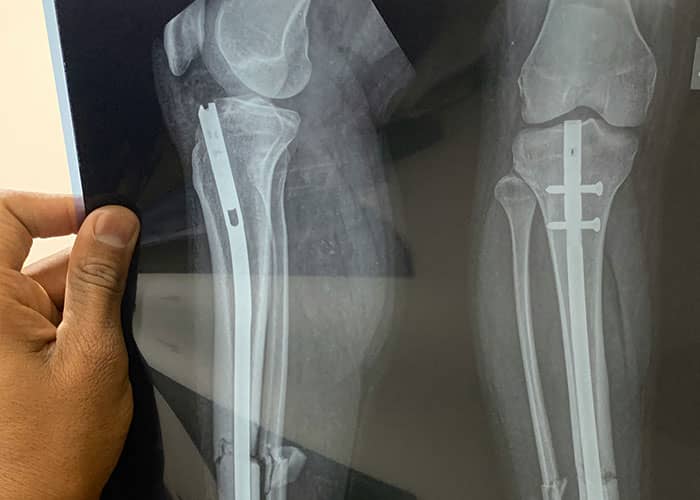

#21

During knee replacement they completely dislocate your knee, put the knee cap to the side, and start measuring and cutting. During tibia replacement part assists help push the tibia forward so you can apply components accurately.

During hip replacement the entire hip is dislocated, and if it’s old posterior approach, your femoral head is sticking out of the wound at like 45 degrees, roughly.

When you get a joint replacement revision, all bets are off. Freaking forget it. There is so much pulling, hammering, drilling. If it’s a hip you can lose so much blood you need a transfusion.

During abdominal surgery if you are reconnecting a patient’s colon, the surgeon will stick a special instrument up your butt to staple the r****m to the intestine. Yes staple.